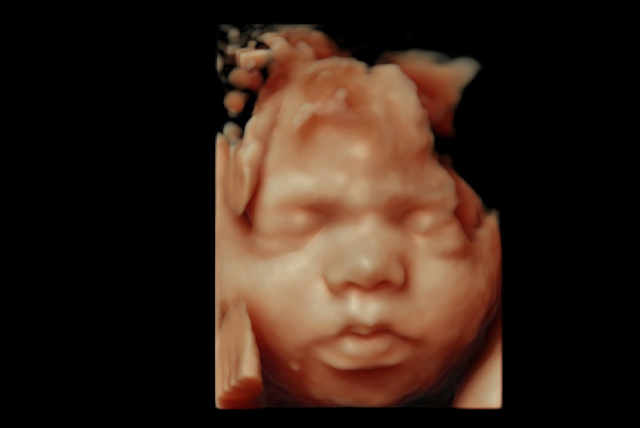

Special 3D Applications

✔️ Fetal Face

✔️ High Definition Live – An extraordinary rendering method generating realistic images of the human fetus